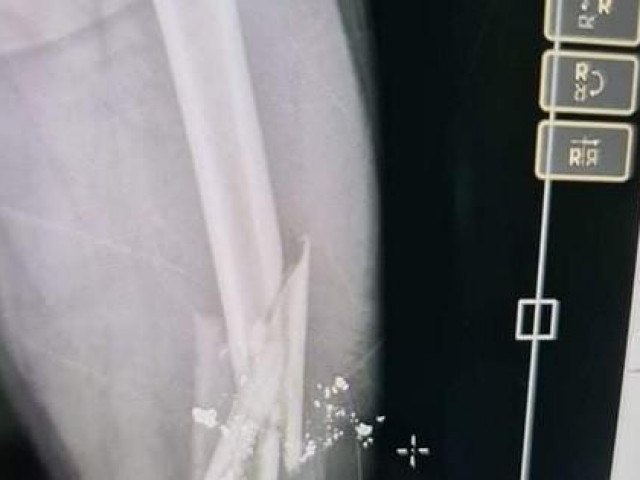

Sau khi gây án nhóm hung thủ nhanh chóng bỏ trốn khỏi hiện trường. Anh Hiếu bị chém đứt cổ tay phải, đang được cấp cứu tại Bệnh viện Đa khoa Khu vực Long Khánh.